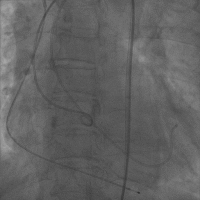

然后进行主动脉根部造影,导丝跨瓣,并进行术前测压评估(Figure 9)。选用大小合适的球囊,进行球囊扩张,评估瓣环上结构,指导选择瓣膜尺寸,这对钙化严重的二叶瓣畸形的患者尤其重要。(Figure 10)

Figure 9

术前测压

Figure 10

3. 主动脉根部造影

4. 导丝跨瓣

5. 测压

最后再次测量跨瓣压差(Figure 12),提示压差较术前显著改善,然后进行主动脉根部造影,提示瓣膜位置理想和形态良好,无明显瓣膜漏。并进行股动脉造影,观察有误血管并发症。(Figure 13)

Figure 12

术后测压

Figure 13

9. 造影结果

10. 股动脉造影